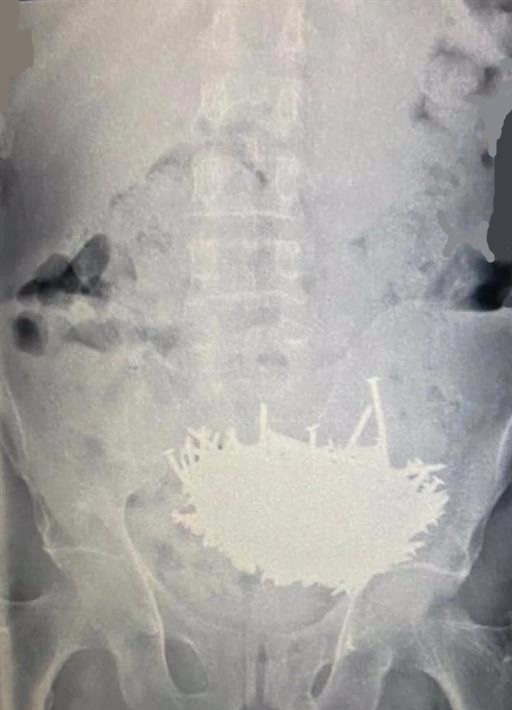

وذكرت تقارير محلية أن الأطباء في مستشفى شرق جدة استقبلوا المريض وبدأوا بفحوصات تقليدية لمعرفة سبب الألم الذي يعاني منه في بطنه، قبل أن تقودهم الفحوصات الإكلينيكية والإشعاعية لوجود عدد كبير من المسامير والزجاج داخل معدة المريض.

واضطر الفريق الطبي لإجراء عمل جراحي طارئ للمريض، لاستخراج تلك المسامير وقطع الزجاج تحت تخدير عام، وهو ما تم بنجاح، وبمجموع 230 مسماراً وقطعا من الزجاج.

وتم تداول صور للمسامير التي تم استخراجها من معدة المريض على نطاق واسع في مواقع التواصل الاجتماعي في المملكة، وسط ذهول من قدرة المريض على ابتلاع ذلك العدد الكبير من الأجسام المعدنية المدببة مع قطع الزجاج الحادة.